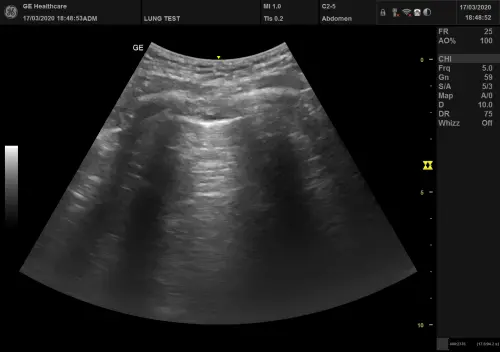

УЗИ легких Киев – современный безопасный метод, позволяющий своевременно выявить заболевания дыхательной системы на ранних стадиях. Клиника Астрамедика на Виноградаре предлагает диагностику легких на аппаратах экспертного класса, что гарантирует максимальную точность результатов.

Наше ультразвуковое исследование легких особенно эффективно при диагностике пневмонии, плеврита, плеврального выпота и контроле восстановления после COVID-19. В медицинском центре созданы комфортные условия для всех пациентов, включая детей и беременных женщин. Записаться на УЗИ легких можно прямо сейчас.

УЗИ легких и плевры – это современный метод диагностики, основанный на применении безопасных звуковых волн высокой частоты. Ультразвуковое исследование помогает визуализировать патологические изменения в тканях легких и УЗИ плевральной полости.

При нормальном состоянии легкие заполнены воздухом, который не проводит ультразвук. Однако при развитии патологических процессов – воспалении, отеке, образовании жидкости – ткани становятся доступными для УЗИ грудной клетки. Именно поэтому диагностика легких УЗИ Киев эффективна для выявления различных заболеваний на ранних стадиях.

Эффективность метода подтверждена многочисленными исследованиями: точность диагностики при плевральном выпоте достигает 97%, при пневмонии – 95%. Сонография легких в Киеве часто назначается как дополнение к рентгенографии.